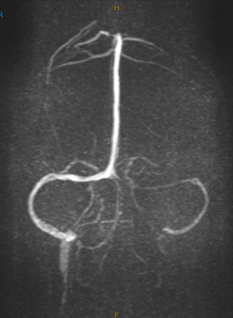

7Jan25 MRI – Hypoplasia of the left transverse sigmoid sinus with possible narrowing at the right sigmoid transverse junction. Flattening of the posterior sclera right >left . Has moderate fluid within the optic nerve sheath,.